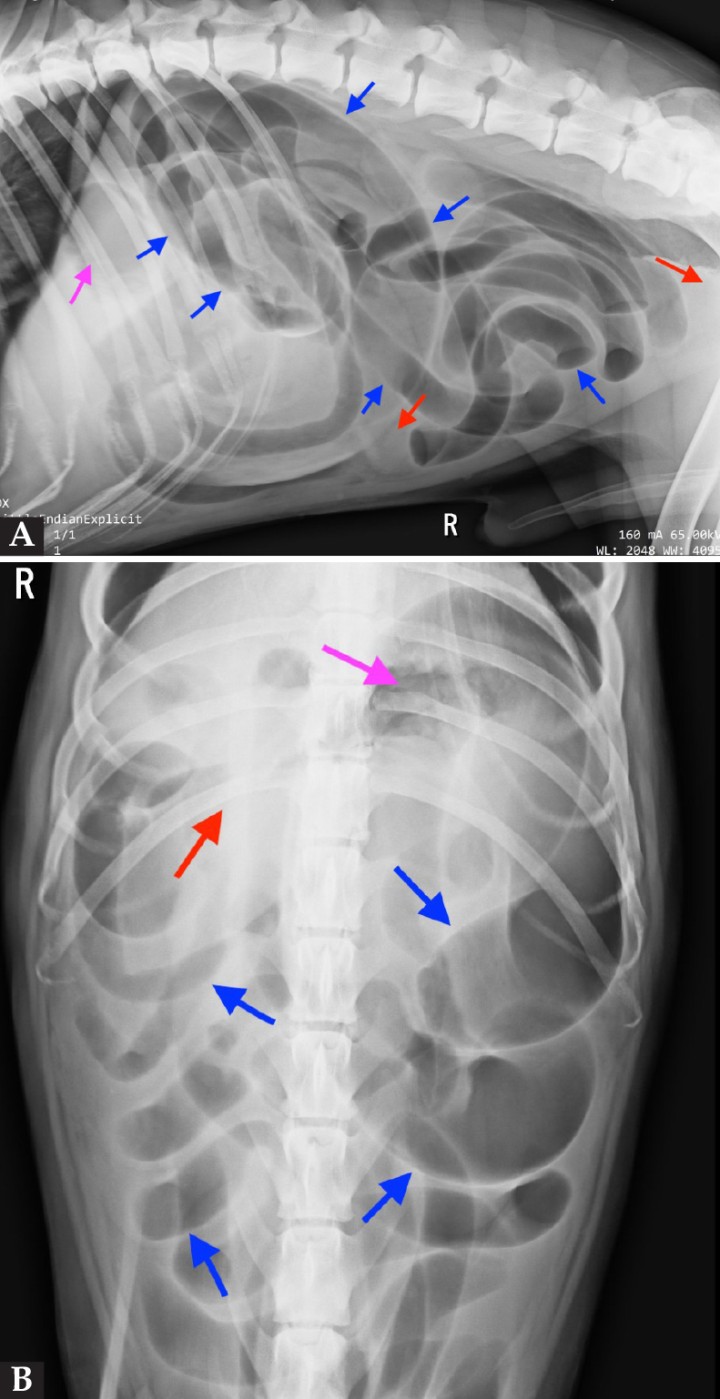

El estómago mantiene una posición normal, con presencia de contenido gas en su interior (flechas violetas; Fig. 2). Se aprecia distensión generalizada de las asas intestinales, con disposición en paralelo de algunas de ellas (flechas azules; Fig. 2). Además, se observa pérdida de definición de serosas en toda la cavidad abdominal (flechas rojas; Fig. 2).

<p>Imagen radiográfica lateral derecha (<strong>A</strong>) y ventrodorsal (<strong>B</strong>) de la cavidad abdominal. En ambas imágenes se observa distensión generalizada del intestino delgado, con contenido gas en su interior y disposición en paralelo de algunas asas (flechas azules), junto con una pérdida de diferenciación de serosas (flechas rojas). Además, se aprecia pérdida de diferenciación de serosas (flechas rojas). El estómago se encuentra en posición anatómica normal (flecha violeta).</p>

Imagen radiográfica lateral derecha (A) y ventrodorsal (B) de la cavidad abdominal. En ambas imágenes se observa distensión generalizada del intestino delgado, con contenido gas en su interior y disposición en paralelo de algunas asas (flechas azules), junto con una pérdida de diferenciación de serosas (flechas rojas). Además, se aprecia pérdida de diferenciación de serosas (flechas rojas). El estómago se encuentra en posición anatómica normal (flecha violeta).

Con el examen radiográfico, podemos obtener un diagnóstico presuntivo cuyos hallazgos más significativos son una distensión generalizada de todas las asas intestinales de manera uniforme y pérdida de diferenciación de serosas, siendo estos compatibles con una obstrucción mecánica o un íleo funcional. La pérdida de diferenciación de serosas se debe a la reacción peritoneal y a la presencia de líquido libre dentro de la cavidad, pero sobre todo al líquido libre que en muchos casos resulta de la perforación intestinal.[ Dennis, R, Kirberger, RM, Barr, F, Wrigley, RH: Gastrointestinal tract. En Dennis, R, Kirberger, RM, Barr, F, Wrigley, RH (ed): Handbook of Small Animal Radiology and Ultrasound, Croydon (UK), Elsevier, 2010; 267-295. , Rautala E, Björkenheim P, Laitinen M: Radiographic and ultrasonographic findings in three surgically confirmed cases of small intestinal ischemia related to mesenteric volvulus or intestinal torsión in dogs. Open J Vet Med 2017; 7: 99-110. , Carbonell Rosello G, Gallach RG, Jimenez Pelaez M: CT diagnosis and management of mesenteric torsión in a dog. Vet Rec Case Rep 2020; 8(3): e001102. ]